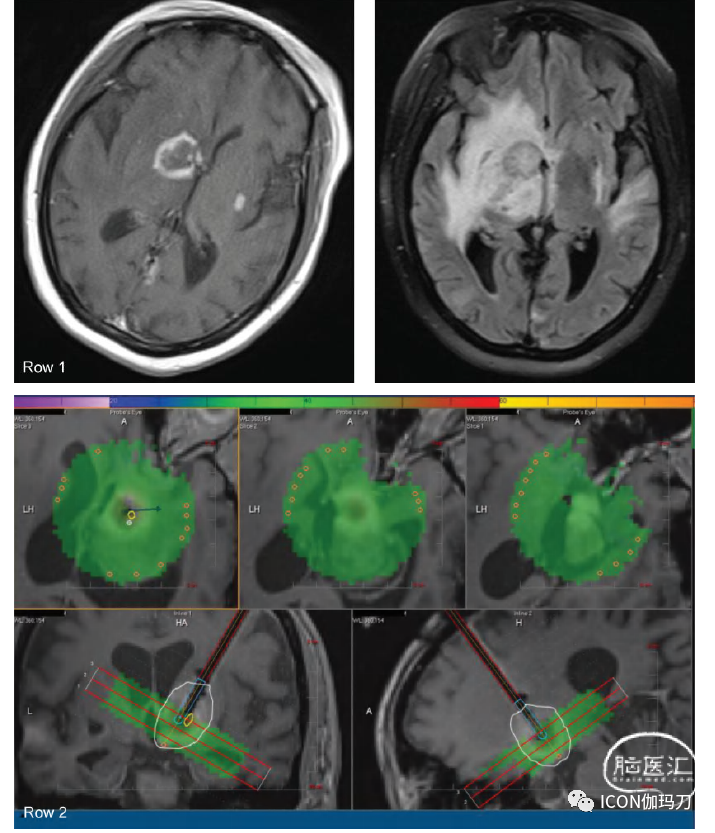

36.4.3 弥撒加权成像

表观弥散系数(Apparent diffusion coefficient,ADC)是基于弥散加权成像(diffusion-weighted imaging, DWI)的MRI序列,也是根据肿瘤细胞的超细胞性来区分肿瘤与放射性坏死。从理论上讲,肿瘤复发应该会导致水扩散受限,从而降低ADC比率,因为与放射性坏死相比,肿瘤复发的细胞数量增加了。然而,复发的肿瘤细胞数量多变,许多再生长的肿瘤有明显的坏死核心,阻碍了明确诊断参数的发展(图36.2)。

图36.2(第1行)图36.1(第2行)显示两个RN病变均未见弥散受限,而图36.1中再次生长的肿瘤也见弥散受限。